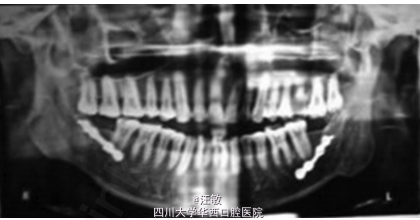

患者自诉过去一年右面部渐进性肿胀,咀嚼和说话困难

检查发现患者面部不对称,开口度为35mm,下颌中线右偏7mm,侧方运动受限。

综合临床和影像诊断为左侧髁突骨软骨瘤

病例中患者有明显的面部不对称,但是全景片并未发现有明显异常。此时计算机断层扫描可以帮助临床医生更加准确的确定病损区域。有趣的是病例中CT扫描可以明显发现左侧髁突增大,但是三维重建却发现左髁突外观正常。 doi:org/10.1016/j.jobcr.2014.12.001